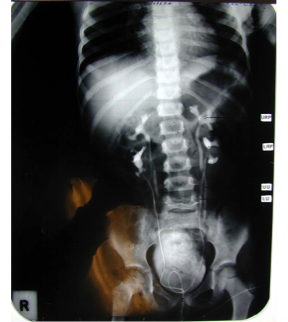

What is that?

Horseshoe Kidney